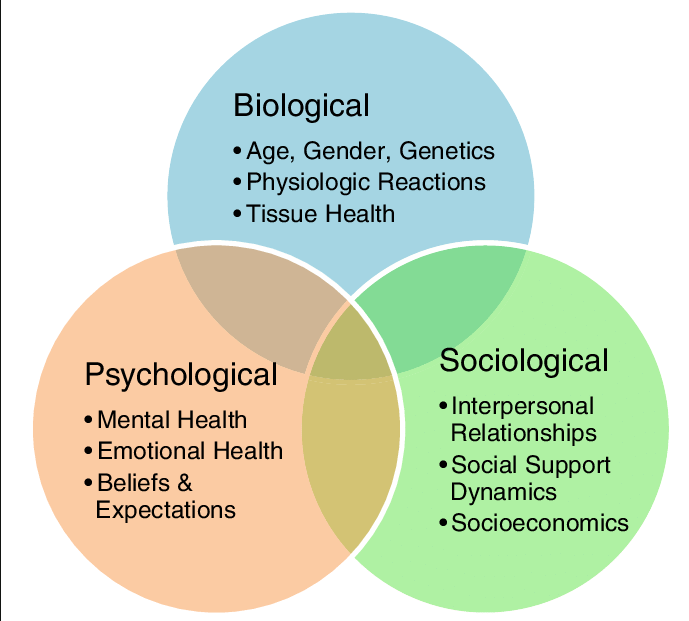

Le podologue est un professionnel de santé spécialisé dans l’étude, la prévention, le diagnostic et enfin la prise en charge et le traitement des affections du pied. La podologie est constituée de 2 branches distinctes mais complémentaires.

La première branche est centrée sur les problèmes unguéaux et cutanés: les ongles incarnés, les mycoses, les verrues, le suivi des personnes diabétiques (contrôle de la sensibilité, de la mobilité, de la peau et des ongles), la modification de la position des orteils grâce à la confection d’orthoplasties (orthèses en silicone réalisées sur mesure), la modification de la courbure des ongles via la mise en place d’orthonyxies (bridges de l’ongle permettant de le redresser et de supprimer les conflits.)

La deuxième branche de la podologie concerne la biomécanique: de manière pratique, elle traite les troubles de la marche, de la course, les problèmes posturaux, l’analyse des muscles et des ligaments en relation avec le pied, les pieds plats/ creux, etc. Celle-ci permet de mettre en relation différentes pathologies du pied avec des segments sous-jacents du corps (genoux, hanches, colonne vertébrale).

Lors de la consultation, le podologue effectue une anamnèse complète, un examen palpatoire des muscles et des ligaments, une analyse de la posture et de la marche. De plus, le podologue définit un traitement sur-mesure et réalise des semelles podologiques adaptées à la pathologie.